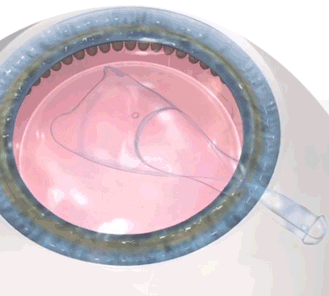

▲ 렌즈삽입술 재수술이 필요한 경우: 수술 후 불가피한 이유로 안내렌즈를 교체 또는 제거해야 하는 경우 렌즈 제거술을 시행합니다.

렌즈삽입술 재수술, 더욱 신중해야 하는 이유

- 삽입한 렌즈까지의 접근이 어렵습니다.

- 렌즈 적출과정에서 렌즈를 놓치는 경우 빈번합니다.

- 각막 내피세포의 손상을 최대한 방지해야합니다.

효과 1.

우수한 고정력과 용이한 진입을 통해 각막 내부의 렌즈를 안정적으로 적출할 수 있음.

효과 2.

렌즈 제거 과정에서 렌즈와 각막 내피의 접촉을 줄여 렌즈에 의해 각막내피세포 손상을 줄일 수 있음.